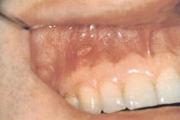

Mehaaniline trauma

pidev põse närimine